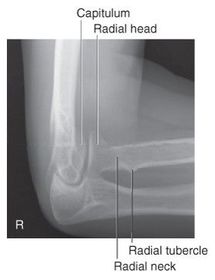

A. radial and coronoid fossas B. capitulum C. trochlea D. coronoid process E. radial tuberosity F. radial neck G. radial head H. trochlear sulcus I. trochlear notch J. olecranon process K. epicondyle L. olecranon fossa

What is in profile for a lateral oblique elbow? radial head radial neck capitulum